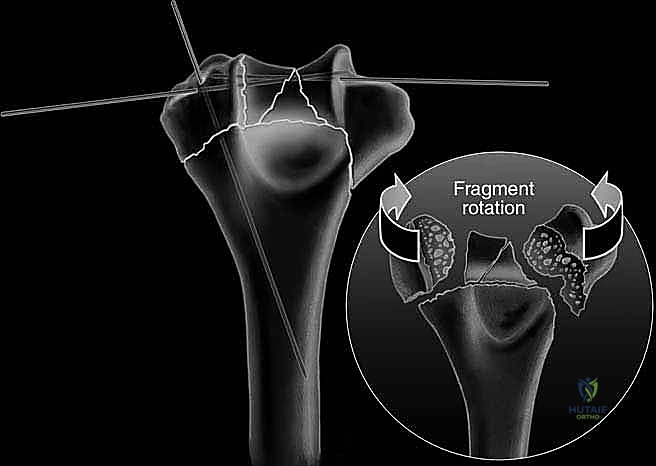

4. الرد المفتوح (Open Reduction) - إعادة تجميع القطع

هنا تبدأ المرحلة الهندسية الدقيقة. يقوم الجراح بتنظيف موقع الكسر من الجلطات الدموية والأنسجة الميتة. ثم يبدأ في إعادة تجميع الشظايا العظمية (كأنها قطع أحجية/بازل). يتم التركيز أولاً على إعادة بناء السطح المفصلي (البكرة والرأس) بدقة تشريحية تامة بنسبة 100% لتجنب خشونة المفصل مستقبلاً. يتم تثبيت هذه القطع مؤقتاً باستخدام أسلاك كيرشنر (K-wires) الدقيقة.